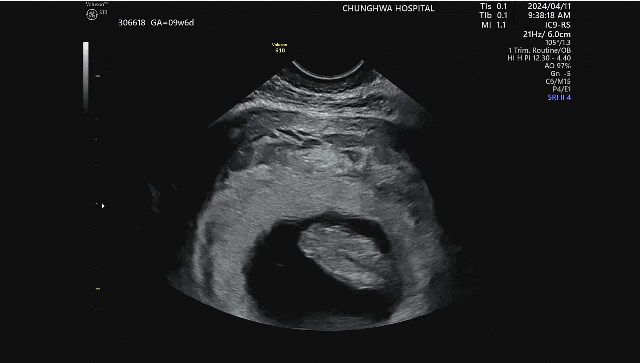

2024년 06월 태교가 따로 있나요. 평화로운 오전 시간에 잔잔한 음악 틀고 만개한 꽃과 함께 독서하는 시간...

2024년 04월 예쁜 우리 엄마 ♡ 올해 2월에 갑상선암 수술이 잡혀있었고, 엄마 퇴원 후 함께 있어주려고 부...

이제 예정일이 한 달 정도 남아 몸은 더 무거워졌지만 아기의 발길질은 매일 신비롭고 사랑스럽다. 이 조그...